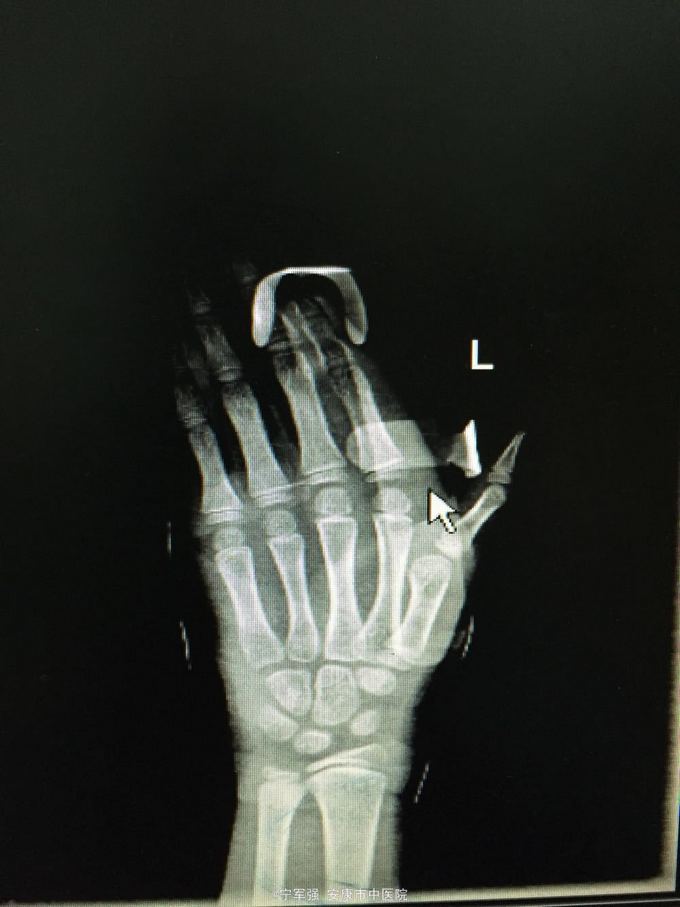

患者8岁,女 扭伤致左手食指肿痛活动受限2小时

患者一般情况良好,左手第二掌指关节处肿胀,弹性固定于伸直位,活动受限,压痛明显,循环尚可

诊断:左手第二掌指关节脱位 处理,予以手法复位失败!考虑关节囊坎顿,阻止复位 予以局麻小切口探查证实,复位脱位,修补关节囊

指骨夹板固定,复查x线显示复位良好 随诊